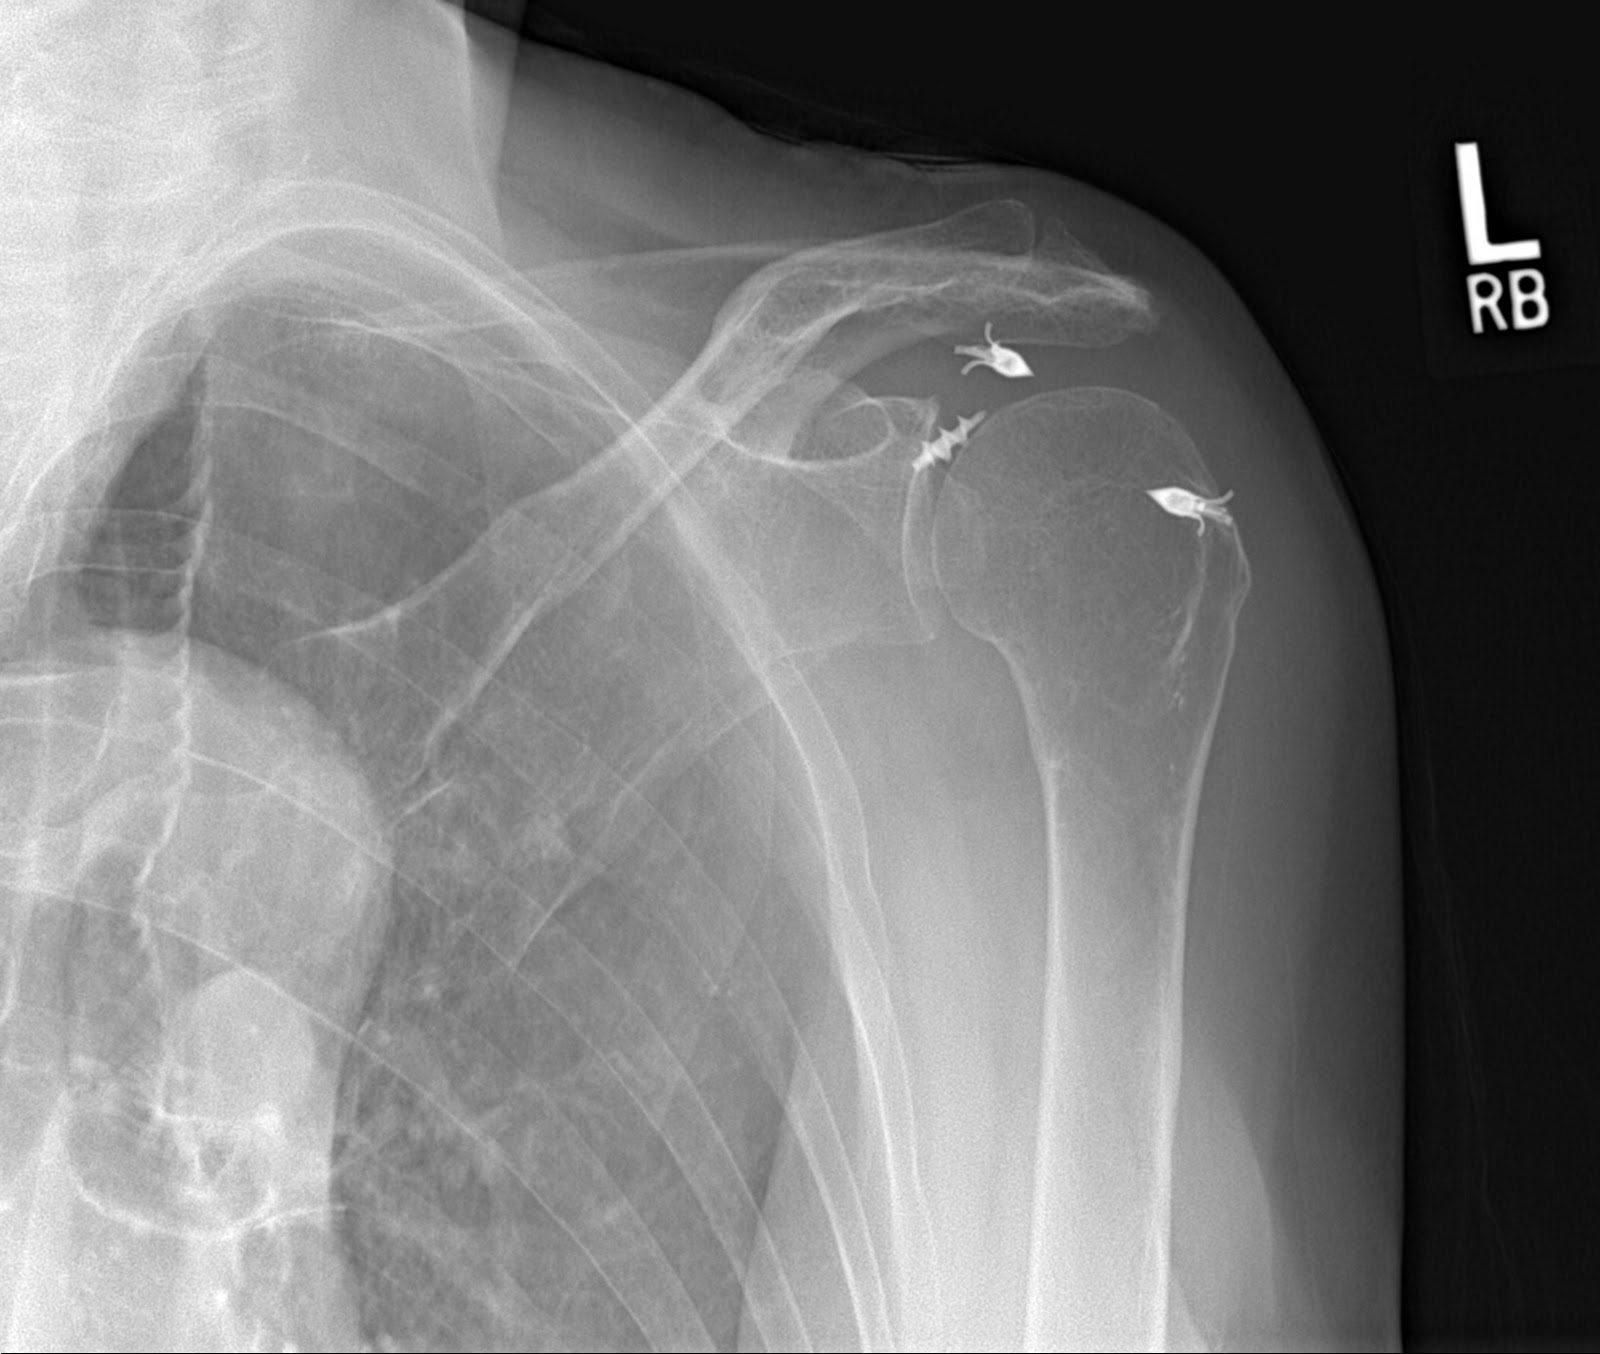

From santabarbarasportsorthopedic.com

AC Joint Repair Shoulder Surgeon Santa Barbara, Santa Maria, Ventura CA Shoulder Replacement X Rays shoulder arthroplasty is the primary treatment of advanced glenohumeral arthritis once conservative measures fail, can restore function to. shoulder replacement removes damaged areas of bone and replaces them with parts made of metal and plastic (implants). Reverse shoulder arthroplasty, total shoulder. shoulder arthroplasties are divided into three categories: They can show loss of the normal joint space. Shoulder Replacement X Rays.